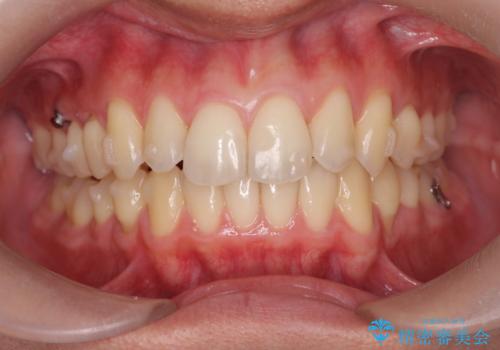

過蓋咬合・上顎前突・叢生を改善するマウスピース矯正

・前歯の深い噛み合わせ (過蓋咬合)

・上顎前突(Angle Class2)

・叢生(がたつき)

以上のような問題点をマウスピース矯正インビザラインとマイクロインプラントを用いて矯正治療を行い改善して行きます。

20時間以上のマウスピース装着、ゴムかけを遵守していただいたおかげでしっかりと噛み合わせ、がたつきの改善を行うことができました。